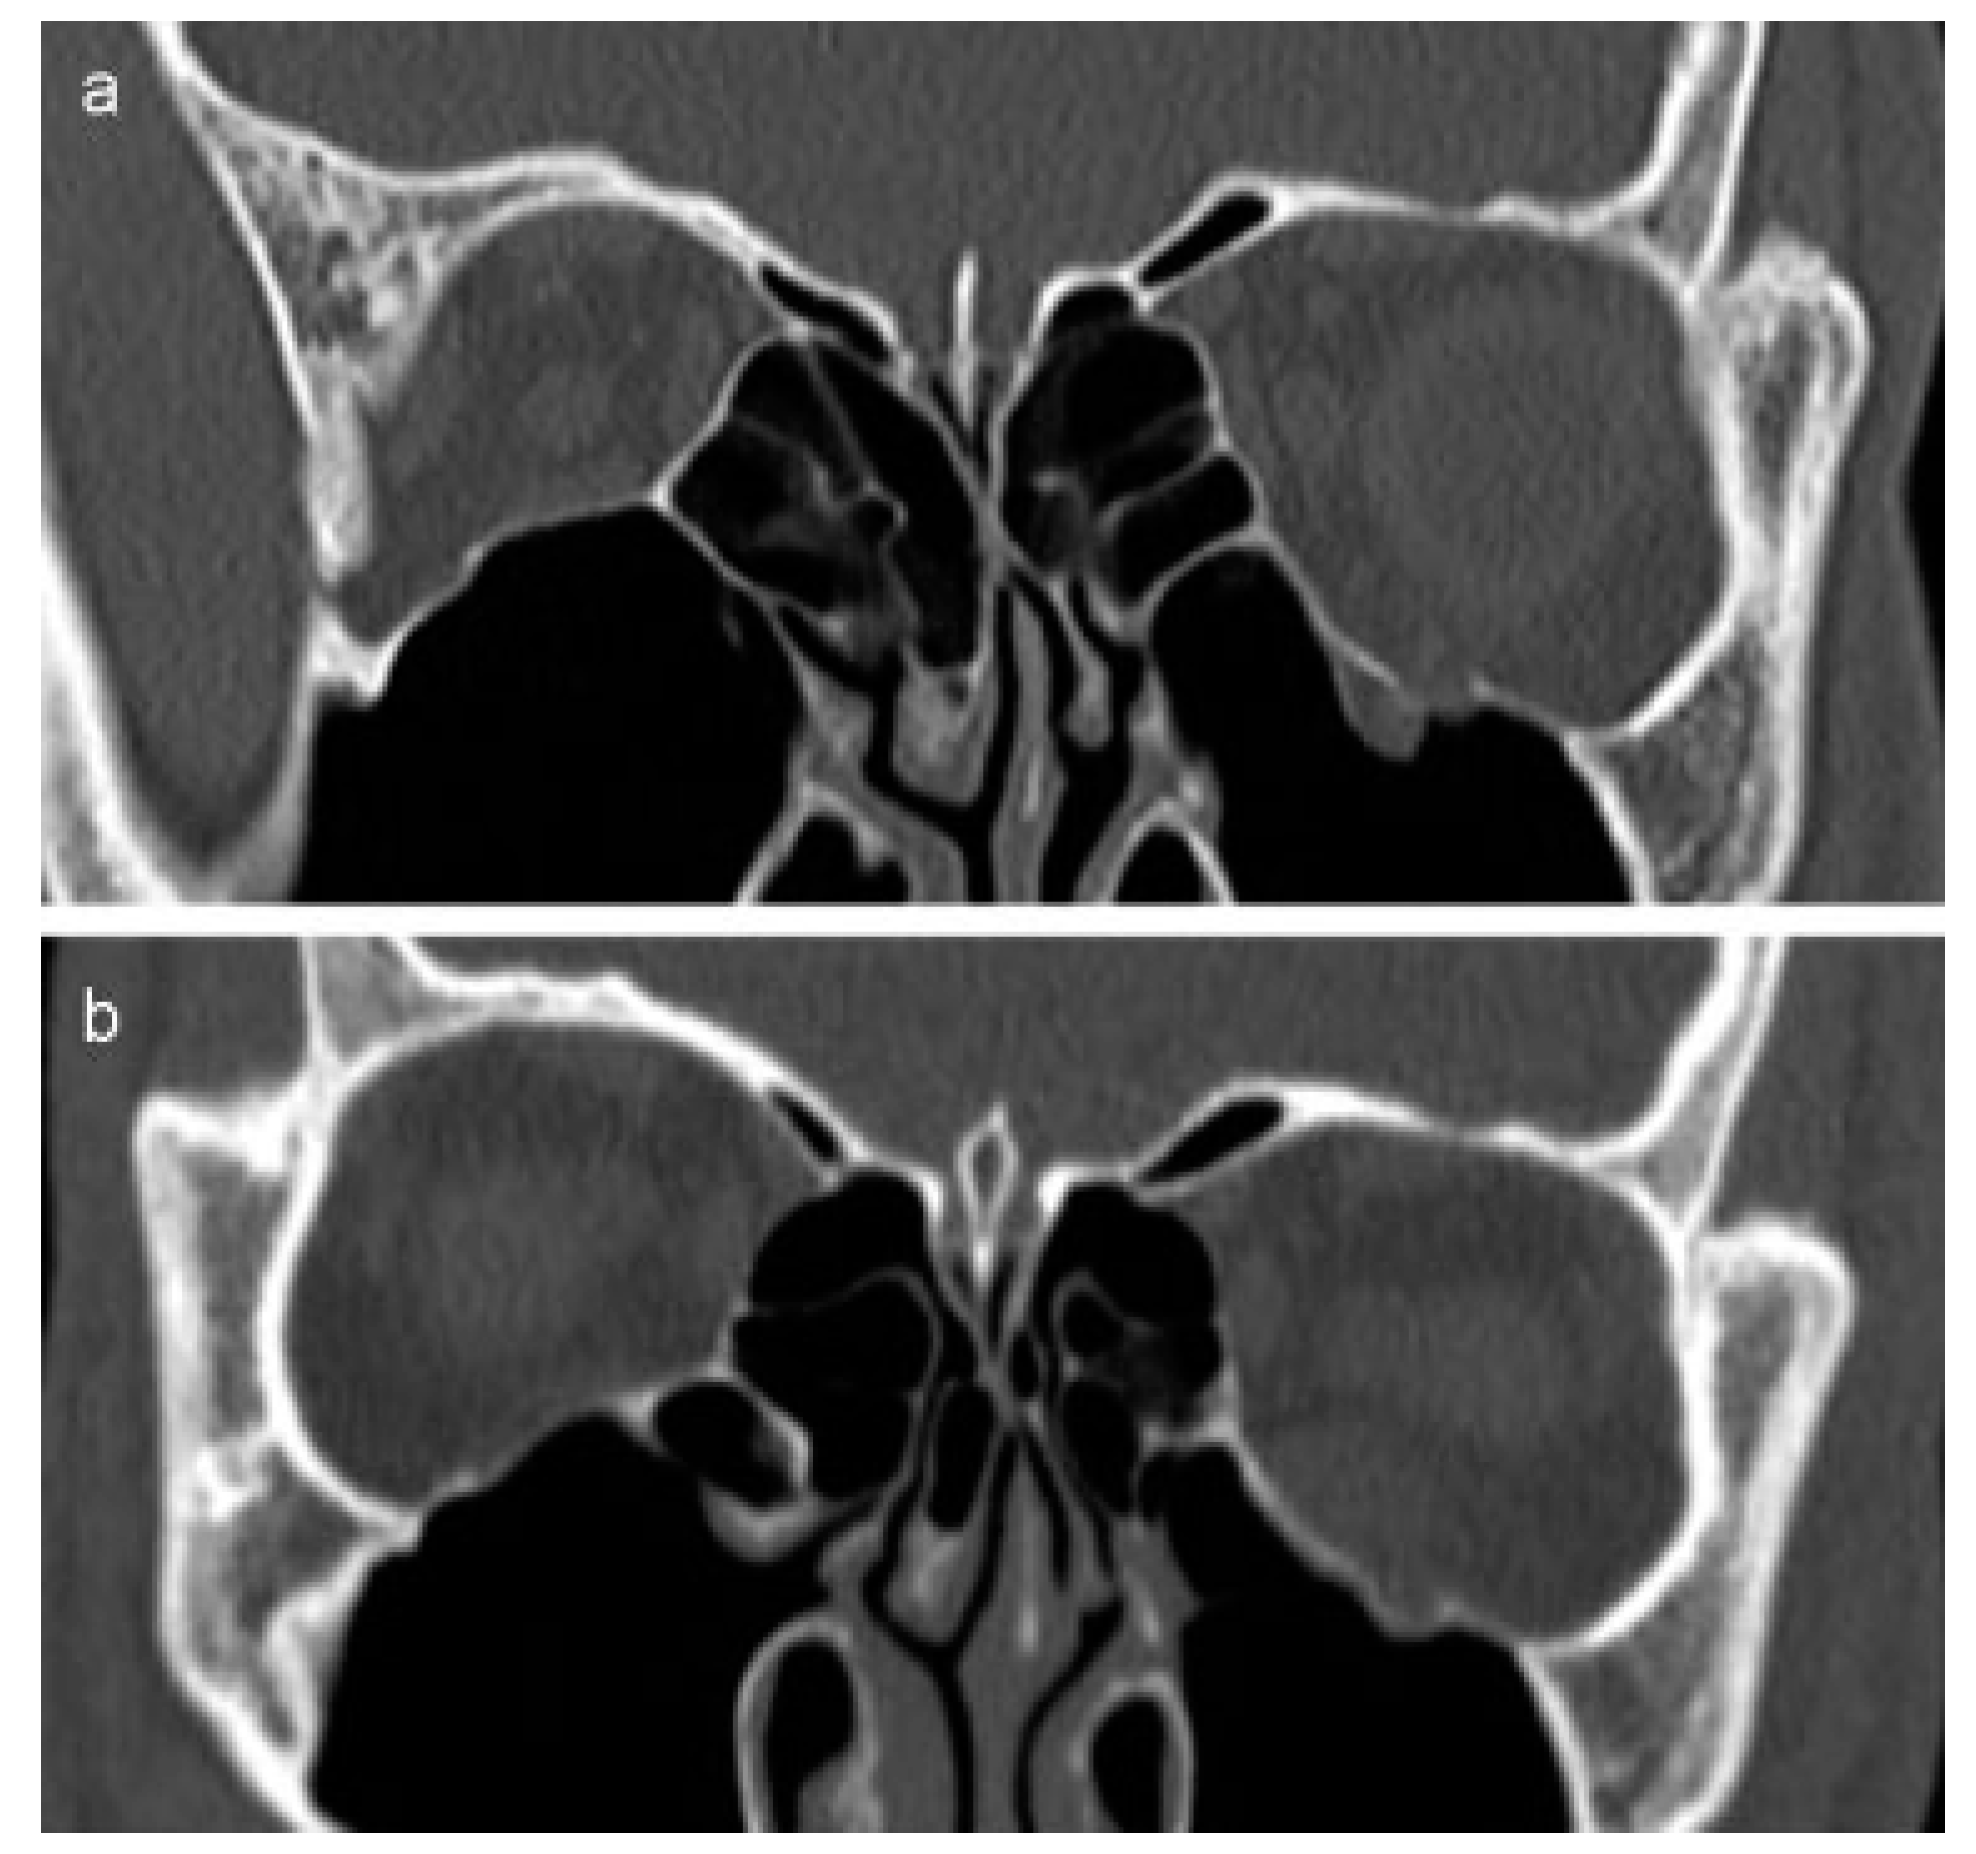

:Case 1

Case 2